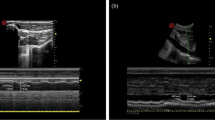

Subclavian vein ultrasonography

Before the SCV examination, all patients would wait in the anesthetic preparation room for ≥ 5 min prior to entering the operating room and were conscious, laying supine, and spontaneously breathing. A 4–15 MHz linear probe of an ultrasound unit (Wisonic, China) was used to perform ultrasound measurements of the right SCV diameter in all patients. To obtain the best view of the SCV during the study, the probe was placed beneath the proximal part of the middle of the clavicle and the area below the clavicle was scanned. Patients were directed to perform a deep, intentional inhalation, followed by a gradual and relaxed exhaling process. After locating the target vein, the change in dynamic diameter over time was recorded using M-mode imaging, which was subsequently used to identify and measure the minimum (dSCVmin) and maximum (dSCVmax) venous dimensions over the respiratory cycle. The SCV Collapsibility Index (SCVCI) and SCV variability (SCVvariability) were calculated using the following formulas; SCVCI = (dSCVmax – dSCVmin)/dSCVmax * 100%, and SCVvariability = (dSCVmax – dSCVmin)/ (dSCVmax + dSCVmin)/2 * 100% [20, 21]. The mean of three measurements was selected. All these measurements were obtained by one anaesthesiologist with extensive sonography experience (Fig. 1).